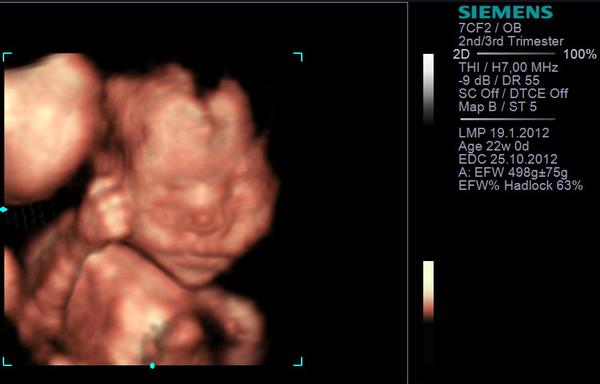

@dadanr morfologiu mas"povinnu"a sluzi na presne zmeranie, vylucenie vyvojovych chyb plodu...robi sa okolo 20tt...4D si platis sama a je to nadstandard - take pekne video s pohybom babatka 😀 my sme boli na kombinacii 4D amorfo u MUDr.Holana a bolo to nadherne...zmeral nas,pozreli sme mocovy mechur, srdce,prietoky, pupocnu snuru ,mozog, dokonca oci a zuby 😀 😀 😀 a ze sme teda obe baby 😀 a potom nam v 4D ukazal tvaricky oboch:

1. foto je 3D v 17tt oboch

2. foto je 4D v 23tt plodu B 😉 -telefonuje 😀